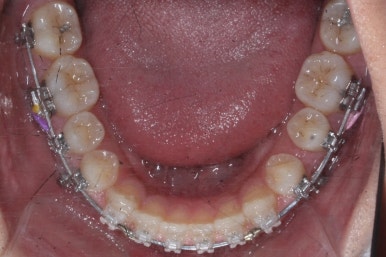

서서히 틈이 줄어들고 있는 것이 보입니다.

벌써 몇 군데는 틈이 다 모였습니다.

이제 거의 다 끝나가고 조금 더 마무리하면 됩니다.

부산치아교정치과에서 치료한 이 사이가 벌어진 틈새교정을 마무리 했을 때의 모습을 보여드리겠습니다.

몰라보게 바뀌었습니다.

틈새가 다 모였고 다시 틈이 벌어지지 말라고 앞니 안쪽에는 유지장치를 달고 마무리를 했습니다.